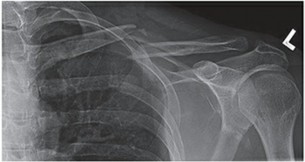

Clavicle Fractures EPIDEMIOLOGY Clavicle fractures account for approximately 2.6% of all fractures and for 44…